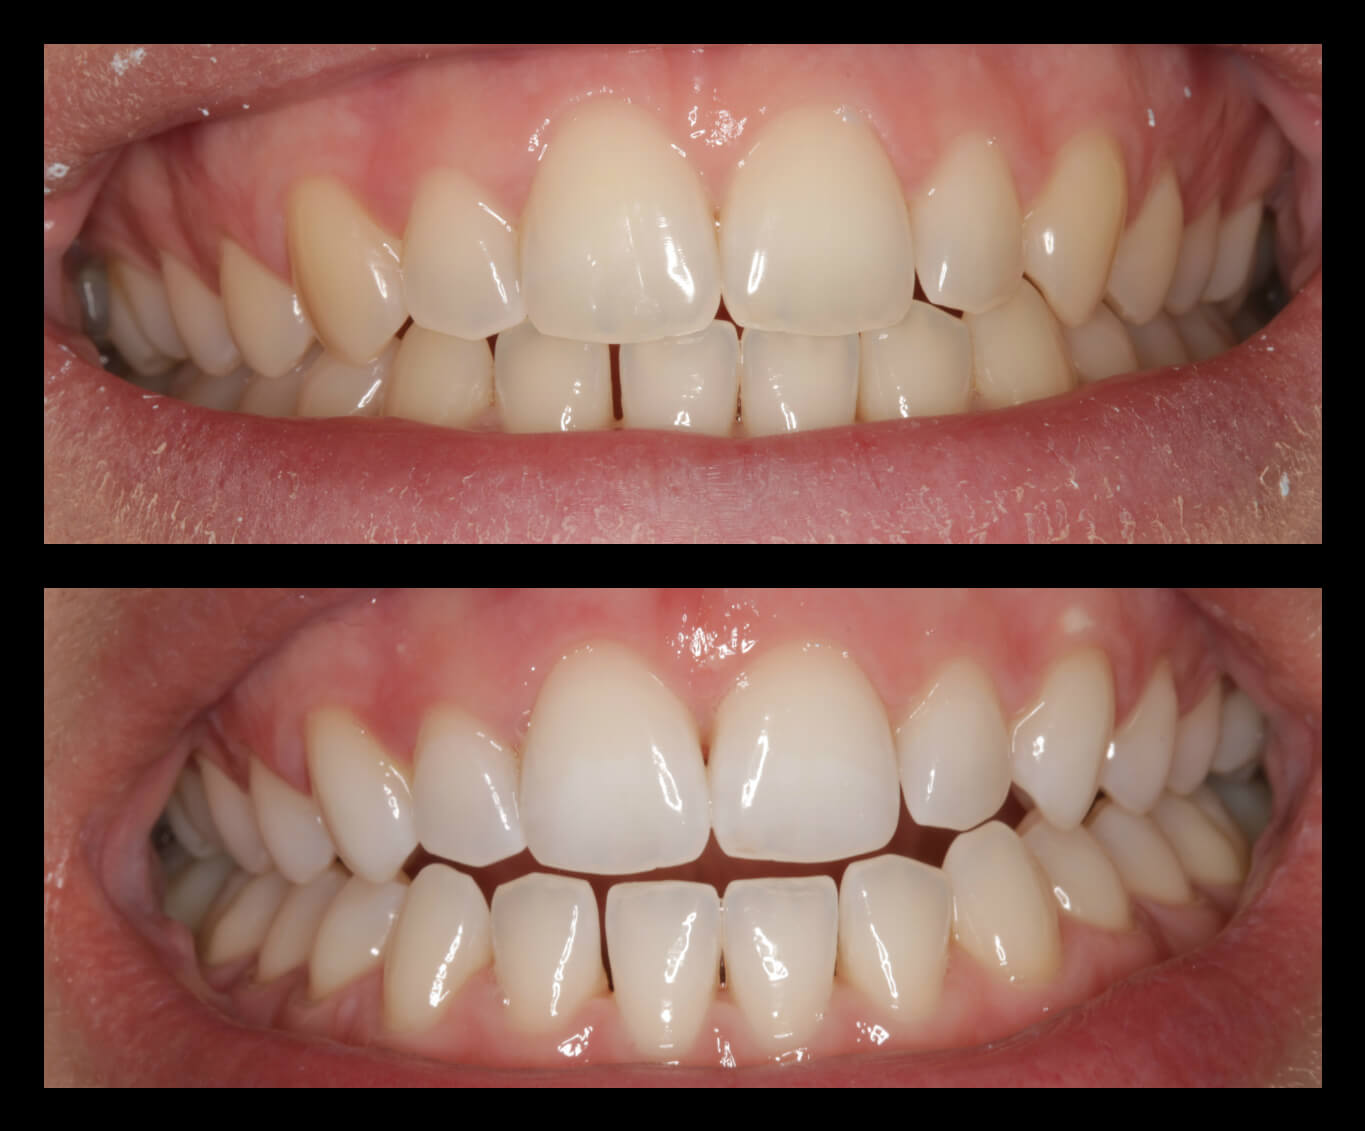

ΠΡΟΣΘΕΤΙΚΕΣ ΑΠΟΚΑΤΑΣΤΑΣΕΙΣ ΜΕ ΣΥΝΔΥΑΣΜΟ ΛΕΥΚΑΝΣΗΣ, ΣΥΝΘΕΤΩΝ ΡΗΤΙΝΩΝ ΚΑΙ ΟΛΟΚΕΡΑΜΙΚΩΝ ΟΨΕΩΝ ΚΑΙ ΣΤΕΦΑΝΩΝ